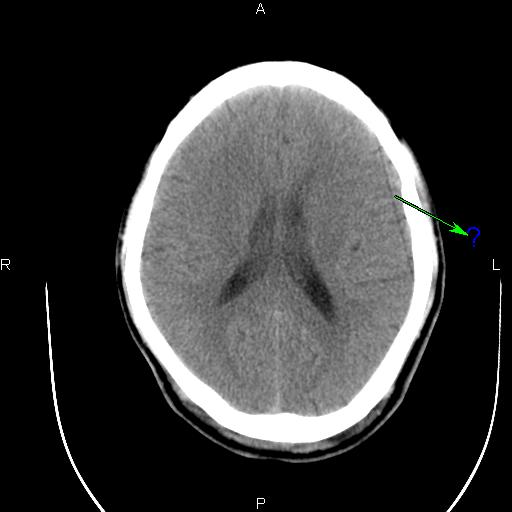

[设备故障求助] 东软ct图像伪影求助

B13F_001.jpg B13E_001.jpg B141_001.jpg B140_001.jpg

这种伪影是怎样造成的?怎样解决呢?

应该是某个通道跳起引起的直线伪影。你可以在过滤成像里检查一下,应该可以看到一跟亮线,找到是某个通道,然后屏蔽就可以了。另外一种方法就是,在ps里,不放线,不旋转,之间看所有的通道值,有没有跳起的?在ps里,放线,不旋转,这样可以看得更加清晰!你可以找到跳起的通道,或你也可以找到相应位置的das板,然后把有问题的das板换到边上,这样也可以解决问题。应该是检测器中间部位的某个das板或是通道引起的伪影